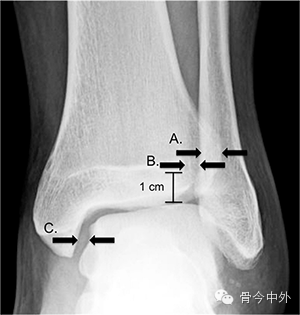

3个影像学检测指标可用于诊断踝关节下胫腓联合损伤(图2):胫腓骨重叠距离,胫腓间隙和内侧关节间隙。胫骨穹窿上方1cm处测量前后位片上胫腓骨重叠大于6mm时提示正常,若前后位X片上重叠小于6mm则提示下胫腓联合损伤。内踝间隙的宽度应和胫骨穹窿/距骨顶间隙相等或略小。在负重位或非负重位X片上胫腓骨重叠距离减小,胫腓骨间隙或者内踝间隙增大均提示下胫腓联合损伤。胫腓骨间隙是影像学上测量最为可靠的指标,因其很少受到下肢和射线成像的角度的影响。

图2:胫腓联合损伤诊断测量线:A,胫腓骨重叠,B,胫腓骨间隙,C,内踝间隙。其中胫腓骨重叠和胫腓骨间隙测量距离胫骨穹窿顶1cm。